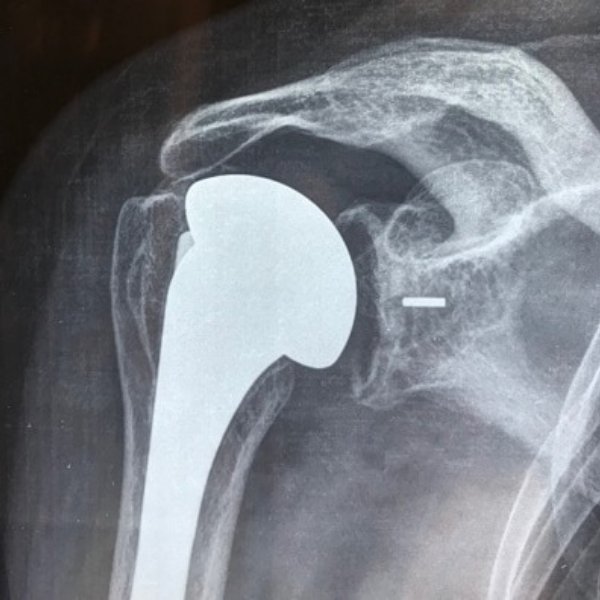

Prótesis de Hombro

Cirugía de Prótesis de Hombro en Santa Cruz

La prótesis de hombro es el tratamiento de elección cuando la articulación ha sufrido un desgaste severo (artrosis) o una fractura compleja que no puede ser reparada. El objetivo es sustituir las superficies dañadas por componentes artificiales que permitan el movimiento suave y, sobre todo, eliminen el dolor que impide el descanso nocturno.

Prótesis Anatómica

Sustituye la anatomía normal. Se utiliza en pacientes con artrosis pero que conservan los tendones del manguito rotador en buen estado. Ofrece un rango de movimiento excepcional.

Prótesis Reversa

Una innovación revolucionaria. Se utiliza cuando los tendones del manguito están rotos de forma irreparable. Cambia la mecánica del hombro para que el músculo deltoides haga el trabajo de levantar el brazo.